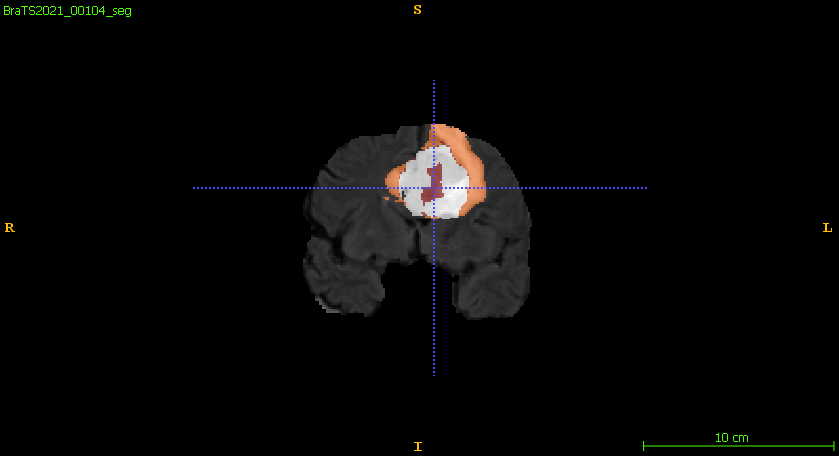

Furthermore, Figure 6 compares the ground truth on different planar views and the predicted segmentation labels corresponding to those views in the training set. The segmentation network demonstrates robust performance, accurately capturing the intricate details of tumor boundaries and structures across all planar views. The achieved DSC for the samples shown is 0.943 for ET, 0.957 for WT, and 0.949 for TC, reflecting the network’s high precision and reliability in segmenting different tumor regions. These results highlight the model’s effectiveness in generating segmentation outputs closely aligned with the ground truth.

Figure 6: Qualitative comparisons include (a–c) input FLAIR images with ground truth overlaid across axial, sagittal, and coronal views, (d–f) ground truth across the planar views, and (g–i) the corresponding predicted segmentation labels from the training set for each view.